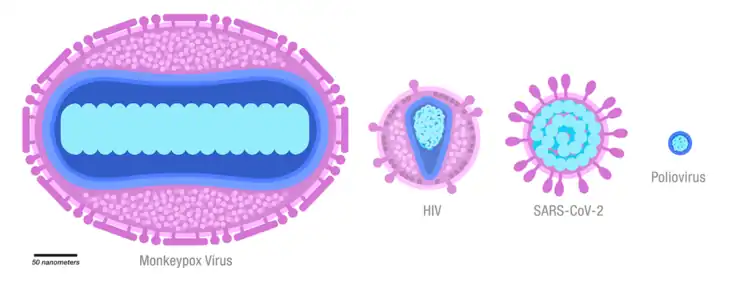

The disease is caused by the monkeypox virus,[lower-alpha 1] a zoonotic virus in the genus Orthopoxvirus. The variola virus, the causative agent of the disease smallpox, is also in this genus.[1] Human-to-human transmission can occur through direct contact with infected skin or body fluids, including sexual contact.[1] People remain infectious from the onset of symptoms until all the lesions have scabbed and healed.[7] It may spread from infected animals by handling infected meat or via bites or scratches.[7] Diagnosis can be confirmed by PCR testing a lesion for the virus' DNA.[1]

Mpox in both humans and animals is caused by infection with the monkeypox virus – a double-stranded DNA virus in the genus Orthopoxvirus, family Poxviridae, making it closely related to the smallpox, cowpox, and vaccinia viruses. The two subtypes of virus are Clade I and Clade II.[1] Clade II is further divided into subclades: Clade IIa and Clade IIb. Cases identified as part of the 2022-2023 global outbreak are caused by Clade IIb.[1] Clade I is largely limited to the DRC and is estimated to cause more severe disease and higher mortality than Clades IIa and IIb.[25]